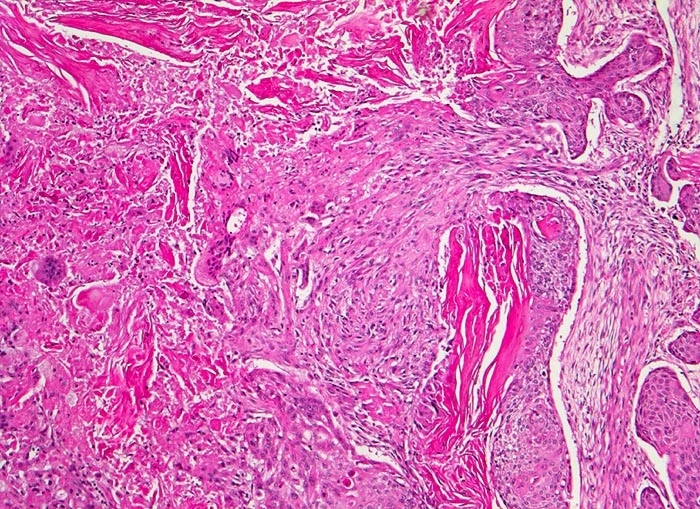

verhornendes Plattenepithelkarzinom

Das Tumorgewebe bildet solide Zellstränge, welche eingebettet sind in ein lockeres desmoplastisches Stroma. Im Zentrum der Zellstränge grosse Mengen von Hornlamellen, welche teilweise nekrotisch zerfallen.

Zentrales Bronchuskarzinom des rechten Lungenoberlappens von 5cm Durchmesser. Lungenoberlappenresektion.

Histologie

100